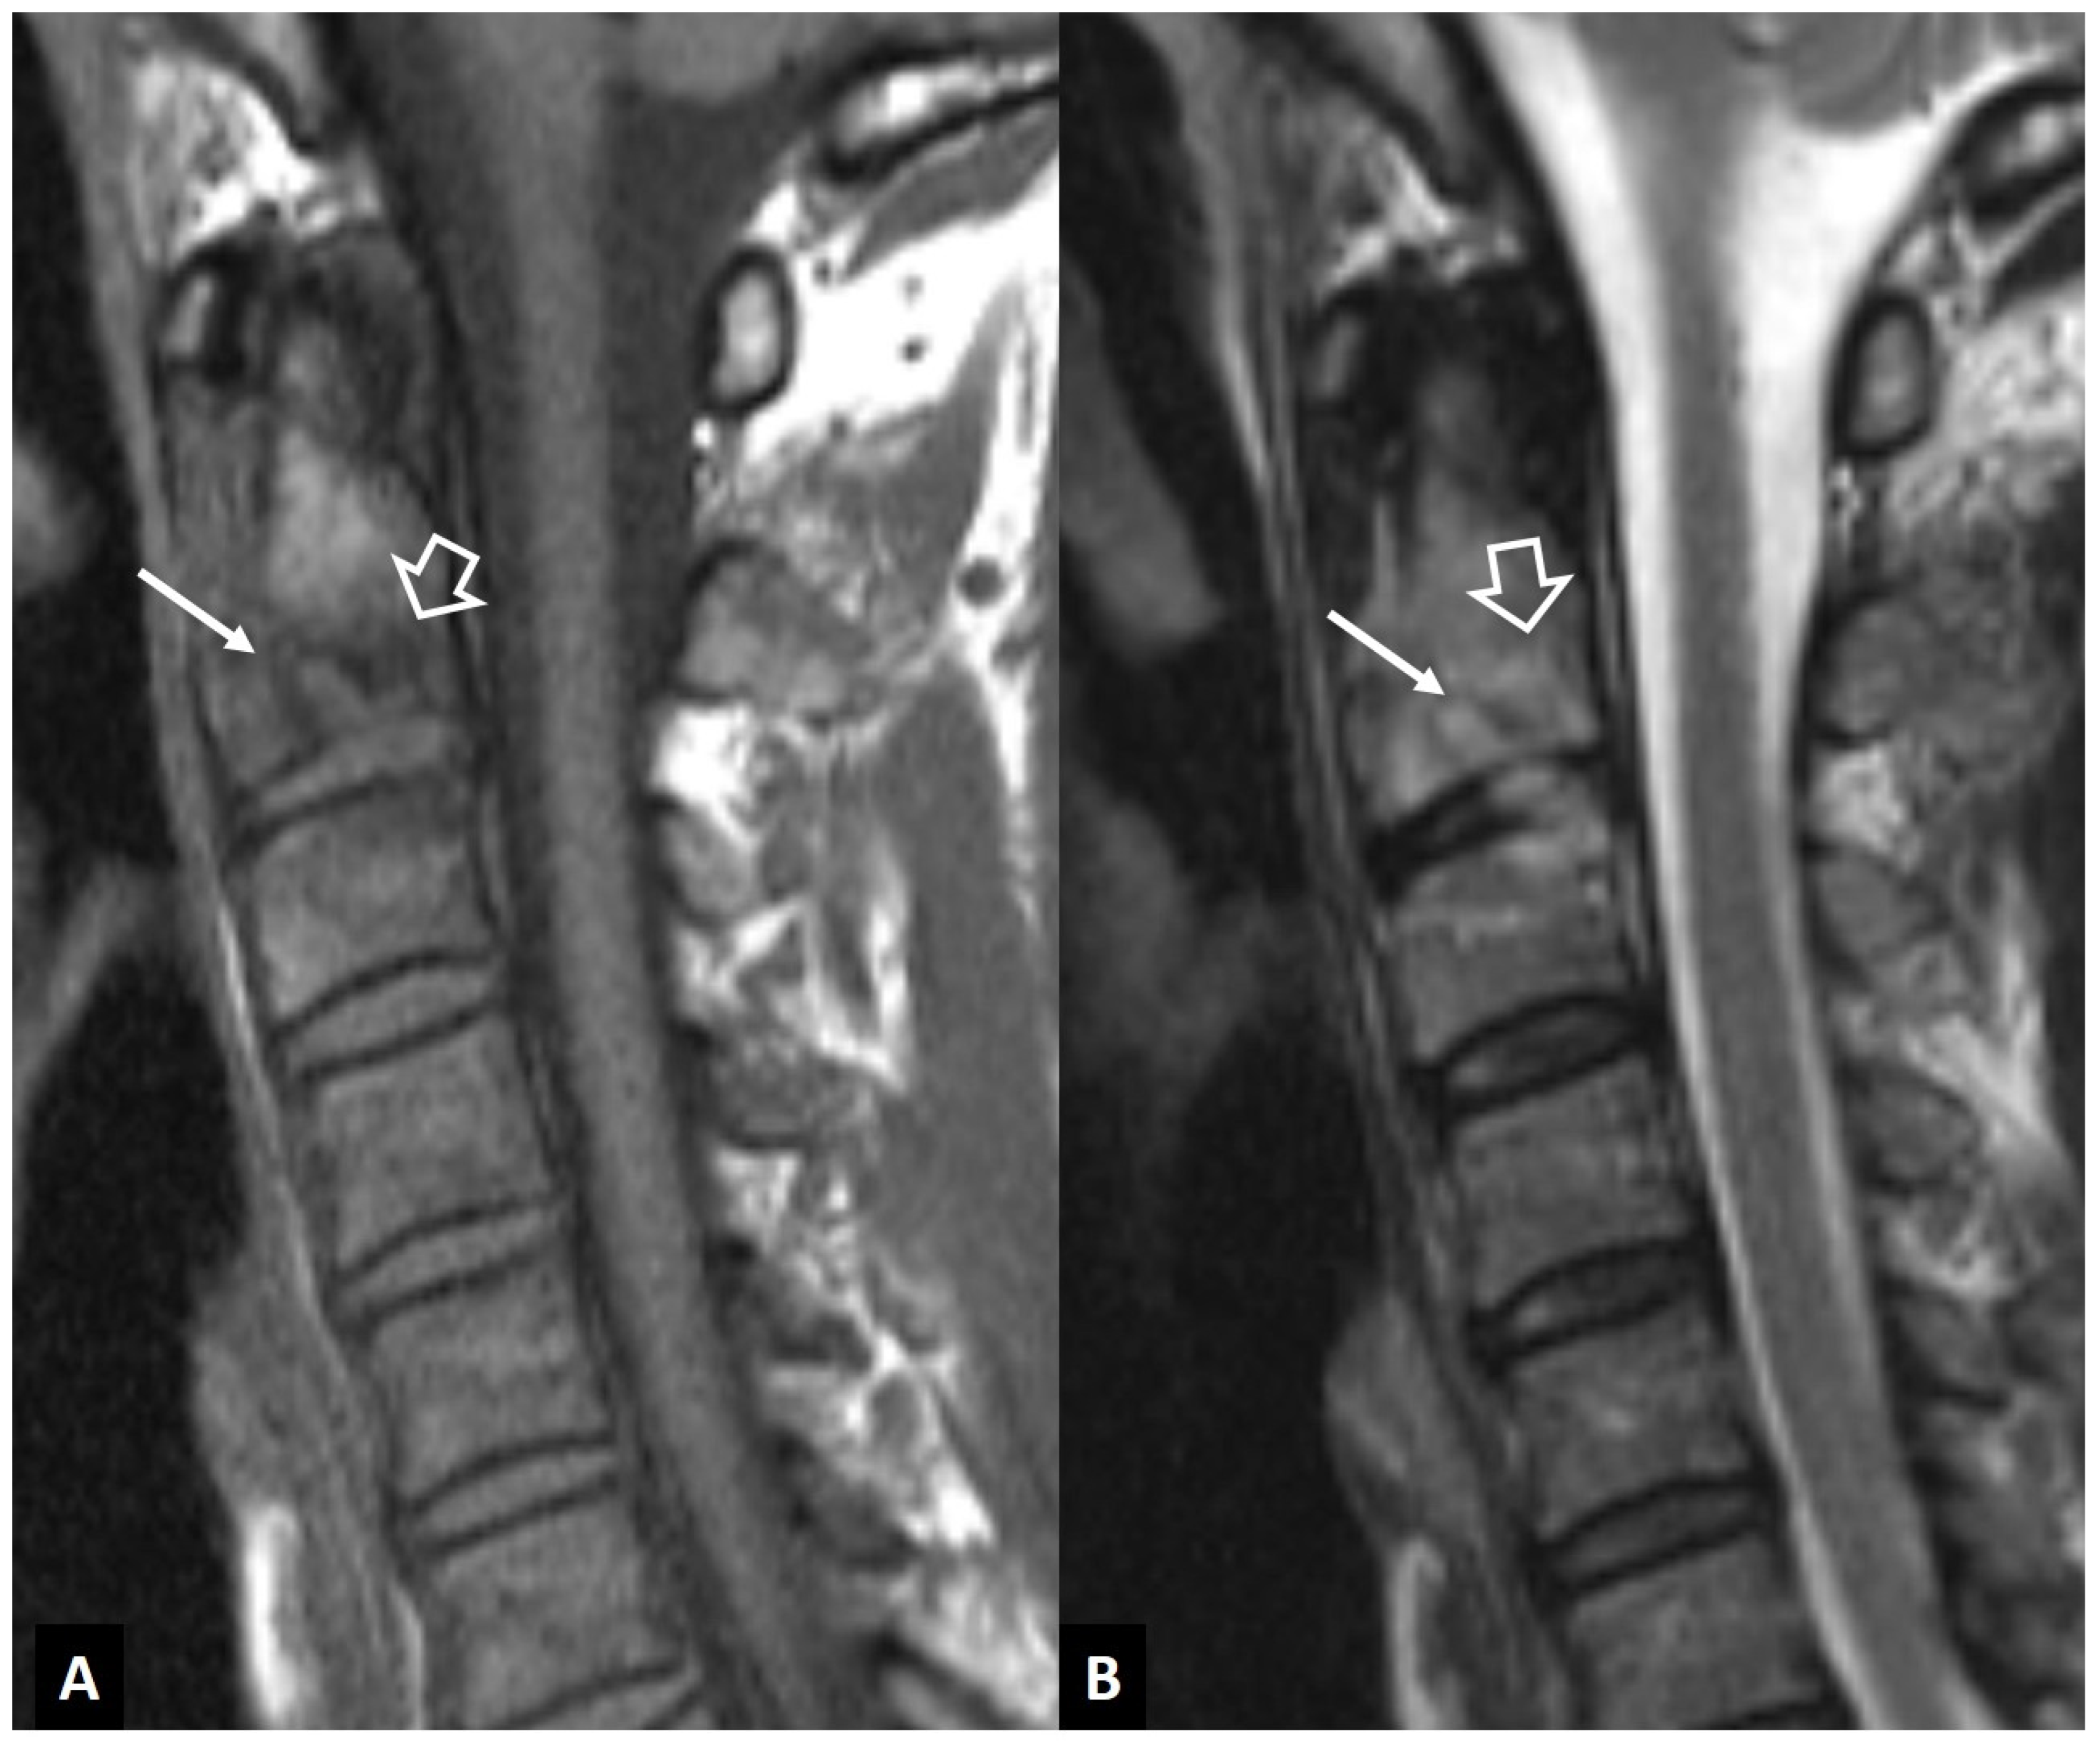

2.1.8. Rheumatoid Arthritis

- Joaquim, A.F.; Appenzeller, S. Cervical spine involvement in rheumatoid arthritis—A systematic review. Autoimmun. Rev. 2014, 13, 1195–1202. [Google Scholar] [CrossRef]